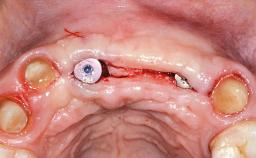

Replacement of Two Central Incisors with Non-Splinted Crowns on Bone-Level Implants

A 27-year-old female patient was referred to the Clinic of Oral Surgery and Stomatology of the University of Bern due to acute pain in the region of her two maxillary central incisors. The patient was in good general health. She reported a bicycle accident approximately 5 years earlier in which teeth 11 and 21 had been traumatized but neither fractured nor displaced. Several weeks after the accident, endodontic treatment was performed on both central incisors, although the patient did not recall the precise reasons for this decision. About 2 years ago, non-vital bleaching had been conducted, in accordance with the “walking-bleach” principle, due to progressive discoloration of teeth 11 and 21.